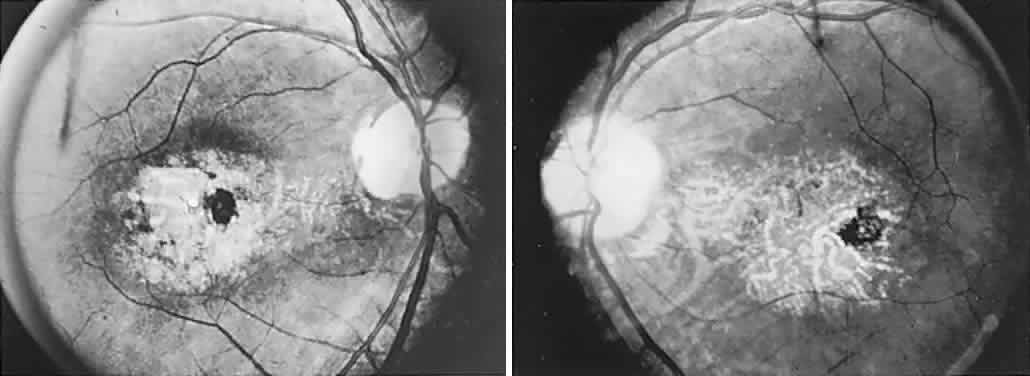

Microangiopathy of the brain, retina, and inner ear (Susac's syndrome) is a rare disorder predominantly affecting women of child-bearing age, but without a specific origin or systemic manifestations. An immune or coagulopathic background is unproved. Patients present with the following: vision loss due to branch retinal arteriolar occlusions with vessel hyperfluorescence on fluorescein angiography, and delayed leakage; hearing loss; multiple CNS infarctions.113 Efficacy of treatment with corticosteroids and immunosuppressive agents is uncertain, but hyperbaric oxygenation has been beneficial in a single case, with rapid visual improvement.114